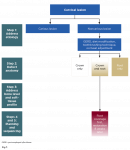

The first step in sequencing in the RSC algorithm is to manage the etiology (Figure 1). This can be done through medical consultation, diet modification, oral hygiene instruction, modification of toothbrushing technique, and occlusal adjustment as needed. Once a plan for management of etiologic agents has been discussed, replacement of hard and soft tissues may be attempted.

The next step involves identifying the extent of the lesion (Figure 1). This can be done by locating the cementoenamel junction (CEJ) of the tooth. In cases where the CEJ is not clinically discernable, an estimation based on knowledge of anatomic measurements of teeth may be used. Once the CEJ is identified, the lesion is categorized into "crown only," "root only," and "combination defect." The crown-only cervical lesion is limited to anatomic crowns, involves enamel and/or coronal dentin of the tooth, and is located coronal to the CEJ. The root-only cervical lesion involves cementum and/or radicular dentin and is located apical to the CEJ. The combination defect extends across the CEJ involving both the crown and exposed root and affecting enamel, cementum, and/or dentin. For carious teeth, the anticipated defect dimension after caries removal must be used to classify the sites as crown-only, root-only, or combination.

In this step an evaluation is made of the clinical examination of the soft tissue, radiographic bone level, and prediction of the amount of root coverage expected (Figure 1). The soft-tissue evaluation includes assessment of gingival phenotype, amount of keratinized tissue width, and depth of vestibule. Sites with thick phenotype and more that 2 mm of keratinized tissue width have shown to have better health indicators, esthetics, and patient comfort.26 Conversely, for sites with thin phenotype and inadequate keratinized tissue width, phenotype enhancement through soft-tissue grafting may be considered to improve periodontal stability, especially in cases of restorations.26 Thus soft-tissue evaluation is important to determine if grafting is necessary. For prediction of root coverage, absence of interdental bone loss with complete papillae fill is a good indicator for obtaining complete root coverage in root-only cervical defects.27-29 Conversely, if there is interdental bone and papillae loss, the predictability for complete root coverage is reduced.27-29 Thus, identifying the interdental bone level and papillae fill is important in estimating the level of root coverage to be gained with a CTG.

Once the assessment of the extent of the cervical lesion and evaluation of soft-tissue anatomy and predictability of root coverage is complete, a suitable treatment plan is selected (Figure 1). Crown-only cervical lesions that involve enamel and/or coronal dentin may be treated with restorative therapy only. A soft-tissue graft may be indicated at such sites first, if the site has a thin phenotype, inadequate keratinized tissue width, and shallow vestibule to achieve a more predictable outcome in the long-term. For lesions limited to the root surface (cementum and/or root dentin), which are commonly associated with gingival recession, only mucogingival surgical procedures may be indicated, provided there is no loss of interdental bone and predictability for complete root coverage is high. However, in cases where there is loss of interdental bone, complete root coverage is not possible.27-29 Such defects are treated as a combined crown and root defect and would need restorative and surgical treatment. When the cervical lesions include both crown and root there is loss of enamel, cementum, and/or dentin. The ideal treatment of such a lesion should involve a combined restorative and surgical approach.

For lesions needing both restorative and surgical correction, a surgical approach should be attempted first, and the restoration may be completed after complete healing has occurred (Figure 1). The objective of the surgery is to position the gingival margin as close to the CEJ as possible. There has been some debate about whether restorative procedures should be done before surgical procedures for NCCLs.4 However, surgical outcomes are dependent on multiple factors and more difficult to predict than restorative outcomes. By performing surgery first, the final result becomes more predictable because the restoration can be adjusted to treat the coronal portion of the lesion and parts of the radicular portion that did not achieve coverage. If the restoration is attempted first and the surgical outcome does not achieve the desired root coverage, the restoration might have to be redone. Further, the use of a CTG increases the soft-tissue thickness and the zone of keratinized tissue. Such a thick gingival phenotype is more favorable to resist inadvertent trauma potentially caused by placement of rubber dam clamps, use of high-speed burs along the margins during tooth preparation and polishing of the restoration, and packing retraction cords during restorative treatment. Conversely, restorative therapy before mucogingival surgery may offer advantages such as better access and visibility and greater control over the emergence profile,4 but the risks outweigh the benefits.